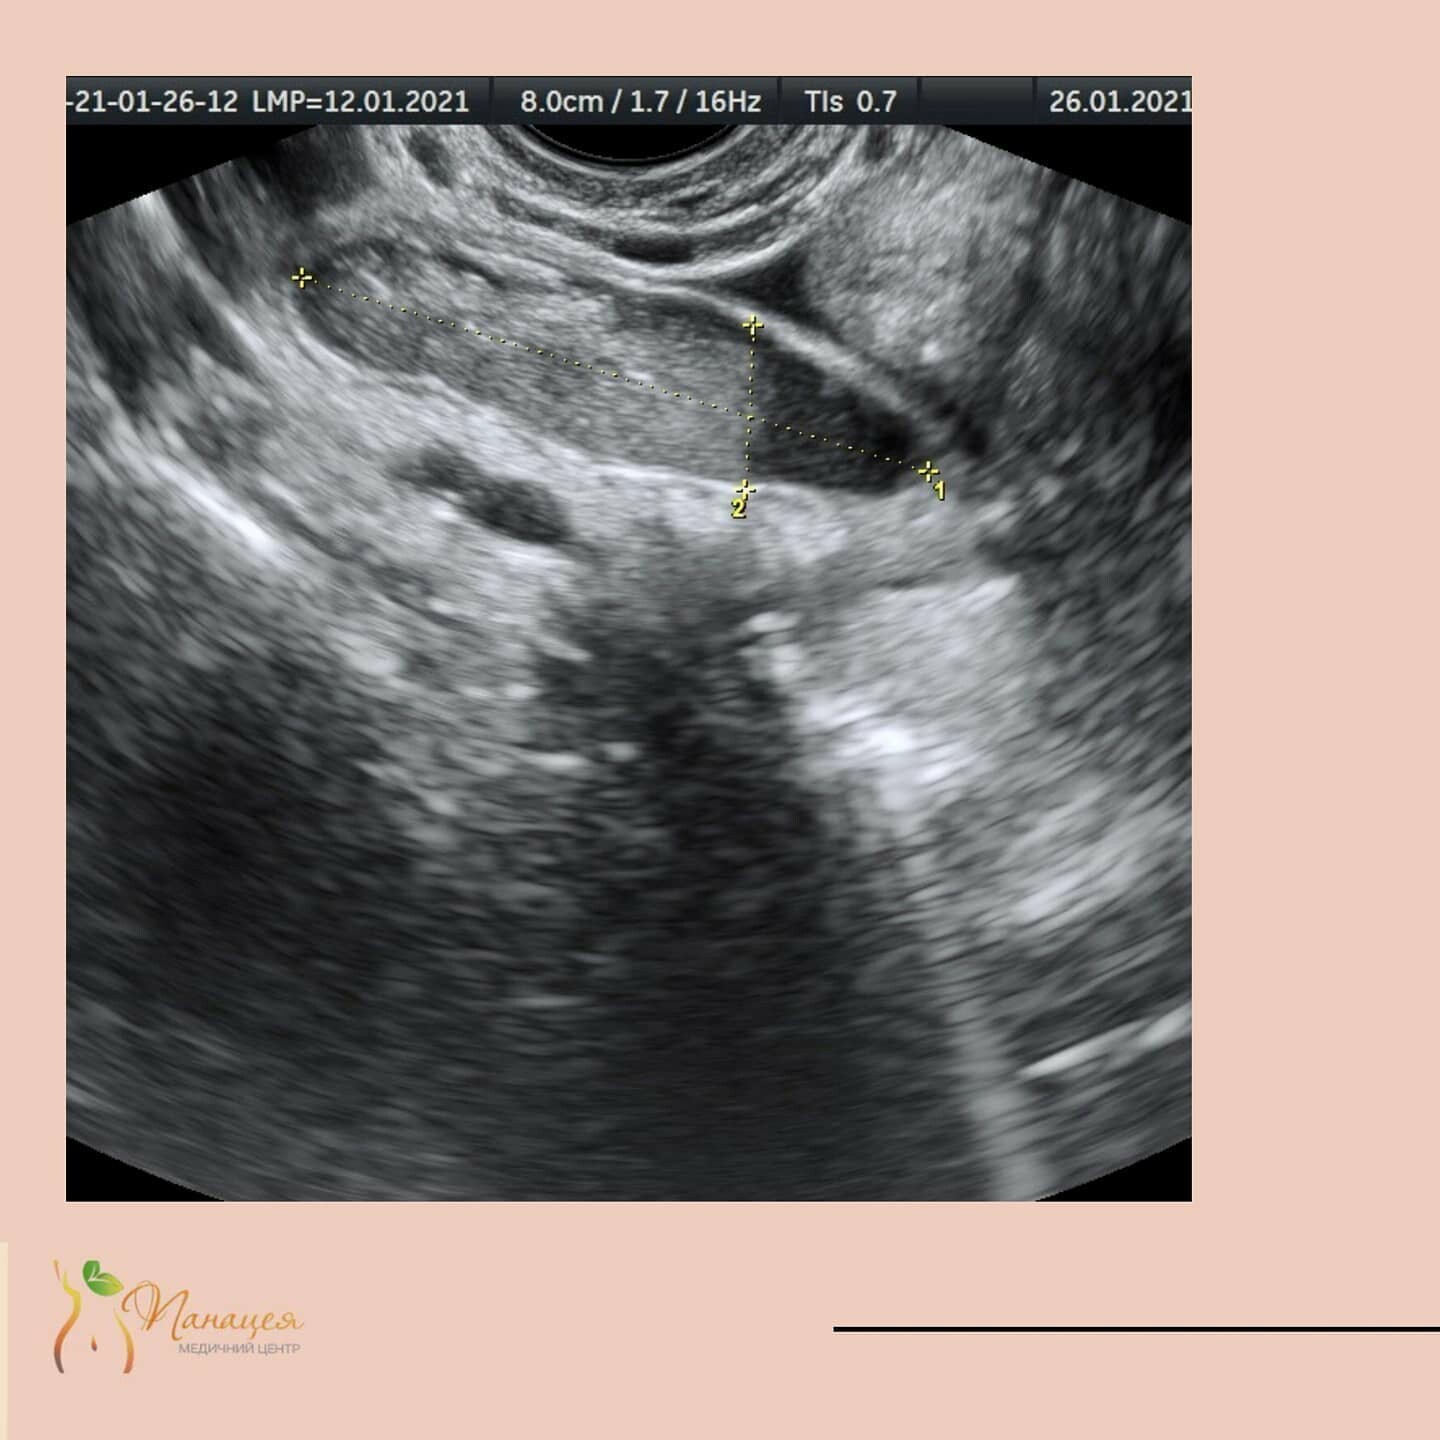

УЗД, або ультразвукова діагностика, відома досить давно, у всіх на слуху, і успішно використовується в різних областях медицини - в гастроентерології та гепатології, гінекології, акушерстві, кардіології, дослідженні вен і артерій, щитовидної і молочних залоз, в урології.

Принцип її дії заснований на ехолокації: датчик, який розташовується на шкірі пацієнта, є одночасно і випромінювачем і приймачем ультразвуку. Ультразвук, вийшовши з датчика, проникає через шкіру і відбивається в тій чи іншій мірі від щільних органів, таких, наприклад, як печінка або нирки. Відбитий звук реєструється тим же датчиком і перетворюється апаратом УЗД в зображення. Цим обумовлена безпека УЗД (випромінюється лише звук, хоч і не чутний людським вухом через дуже високу частоту коливань). Метод абсолютно безпечний навіть при вагітності і у маленьких дітей. Ще й недорогий. Дослідження займає нетривалий час і результат відомий відразу. Єдиний недолік - не всі органи людського тіла можна досліджувати за допомогою УЗД, а тільки щільні, які не містять повітря (наприклад, печінка, селезінка, нирки або підшлункова залоза), оскільки звук «повітряними» органами (такими, наприклад, як легены) НЕ віддзеркалюється.